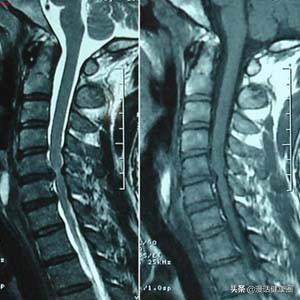

不良姿勢やスポーツ障害により、頸椎の生理的湾曲矯正が誘発された頸椎症

外から見ると、人間の首はまっすぐに見えるが、実際には頸椎は湾曲している。私たちの背骨は直線ではなく、頸部と腰部は前方に凸、胸部と仙骨部は後方に凸という4つの生理的湾曲を持つS字型をしており、これによって背骨の可動性と体重を支える機能が向上している。

数ある頚椎疾患の中でも、頚椎椎間板ヘルニアは一般に最もよく知られている疾患です。頚椎椎間板ヘルニアはどのようにして起こるのでしょうか?前述したように、頚椎の椎間板は20歳を過ぎると変性が始まり、椎間板内部の髄核はもともと水分や弾力性に富んでいるため、クッション性や衝撃吸収効果が高いのですが、変性が進むと髄核の水分が失われ、弾力性が低下してもろくなり、運動刺激で椎間板の外側にある線維性環状体が破裂しやすくなり、髄核が線維性環状体から破裂して突出し、隣の脊髄を圧迫します、髄核が線維性環状体から突出し、隣接する脊髄や神経、血管などの組織を圧迫することで、対応する部位に痛みやしびれなどの症状が出ることを椎間板ヘルニアといいます。

一般に頚椎症は、椎間板の退行性変化から始まり、頚椎椎間板ヘルニア、頚椎椎間板狭窄症、頚椎症性脊髄症、後縦靭帯骨化症というように連動して進行し、最終的には脊髄、神経、血管など頚椎周辺の組織の圧迫や刺激によって生じる痛みやしびれという結果に至ると考えられています。これをもとに、圧迫や刺激を受ける脊髄の各部位に応じて頚椎症にはいくつかのタイプがある: